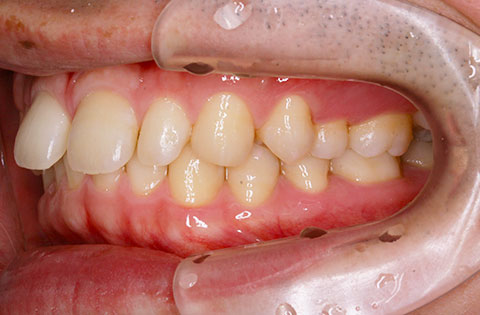

矯正前 右側

矯正後 右側